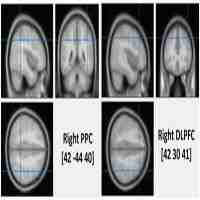

| Abstract | Traditionally, it has been thought that probabilistic category learning, one of the implicit memory functions, is dependent on the basal ganglia. However, there is growing evidence indicating the involvement of the dorsolateral prefrontal cortex (DLPFC) in probabilistic category learning. In order to identify the causal role of DLPFC in probabilistic category learning, we investigated whether repetitive transcranial magnetic stimulation (rTMS) over the left DLPFC influences the learning ability in healthy subjects using the weather prediction task (WPT). Application of 10 Hz rTMS over the left DLPFC induced significant improvement in the total hit rate during the total trials of the WPT, compared with sham stimulation. Specifically, the improvement was significant in the early and late learning blocks of the WPT, but not in the intermediate block of learning. These results indicate that the left DLPFC may play an important role in probabilistic category learning, possibly by influencing not only on embodied information application in late stage of the learning but also on memory encoding for working memory demands in early stage of the learning via frontostriatal and frontohippocampal circuits, respectively. They also may lend support to the possibility that rTMS can improve implicit learning ability in patients with basal ganglia disorders. |